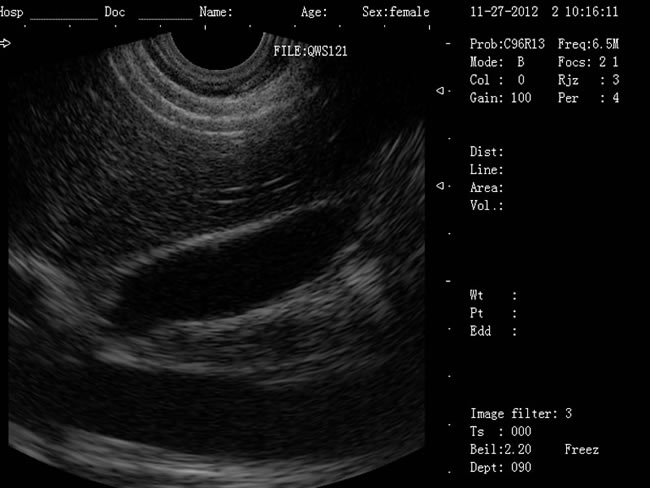

DW-400 全數(shù)字可視人流機(jī)

• 功能特點(diǎn): 定位精確 手術(shù)效率高:實(shí)時(shí)動(dòng)態(tài)頻率掃描等全數(shù)字超聲成像技術(shù)、生成精確的圖像引導(dǎo)手術(shù)器械迅速到大手術(shù)位置,避免損傷子宮內(nèi)膜和子宮穿孔的現(xiàn)象,即減輕了患者的痛苦又極大提高了手術(shù)效率。 高密度全數(shù)字波束形成:采用全新一代混頻技術(shù)、數(shù)字嵌入系統(tǒng)及數(shù)字整序技術(shù) 有效提升系統(tǒng)的穩(wěn)定性、可靠性:實(shí)時(shí)動(dòng)態(tài)孔徑成像,充分保證圖像的精度和清晰度。

定位精確 手術(shù)效率高:實(shí)時(shí)動(dòng)態(tài)頻率掃描等全數(shù)字超聲成像技術(shù)、生成精確的圖像引導(dǎo)手術(shù)器械迅速到大手術(shù)位置,避免損傷子宮內(nèi)膜和子宮穿孔的現(xiàn)象,即減輕了患者的痛苦又極大提高了手術(shù)效率。

有效提升系統(tǒng)的穩(wěn)定性、可靠性:實(shí)時(shí)動(dòng)態(tài)孔徑成像,充分保證圖像的精度和清晰度

a) CXA10R 腔內(nèi)探頭:152º可視可調(diào);